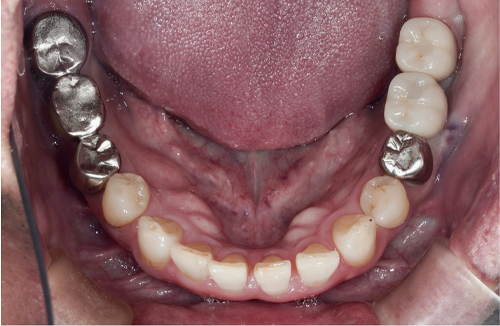

当院のインプラント治療例

― 他院で「難しい」と言われたケースにも対応 ―

同じように「奥歯が噛めない」「骨が足りないと言われた」お悩みをお持ちの方は、無料相談でご相談ください。

インプラント治療において私達が大切にしていることは、なぜ歯を失ってしまったかを徹底的に診断することです。

「虫歯で歯を失ってしまったのか?」、「歯周病で歯を失ってしまったのか?」、「かみ合わせの問題があるのかどうか?」等を診断することは非常に大事なことなのです。これらの事は、歯を失ったことは同じですが状況は全く異なるのです。

私達は歯を失ってしまった原因を追求し、インプラント治療、虫歯治療、歯周病治療、矯正治療、根管治療等の治療を組み合わせ総合的に治療計画を立てて治療を行っていきます。